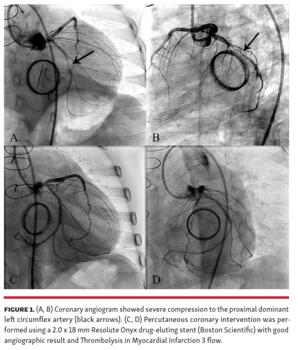

A 4-year-old girl with congenital mitral regurgitation status post mechanical mitral valve replacement (MVR) using a 16 mm Carbomedics valve (LivaNova) at the age of 5 months underwent a redo MVR using a 21 mm aortic prosthesis implanted in an inverted position for progressed increased mitral valve gradient due to pannus formation. Post operatively, echocardiogram showed good mitral valve prosthesis function with severe depressed left ventricular function (ejection fraction, 19%) and markedly segmental dyskinesia in the lateral wall. Coronary angiogram showed severe compression to the proximal dominant left circumflex artery (Figures 1A and 1B; Videos 1 and 2). Percutaneous coronary intervention was performed using a 2.0 x 18 mm Resolute Onyx drug-eluting stent (Boston Scientific) with good angiographic result and Thrombolysis in Myocardial Infarction 3 flow (Figures 1C and 1D; Videos 3 and 4). At 3-month follow-up, the patient was symptom free and the left ventricular function recovered.